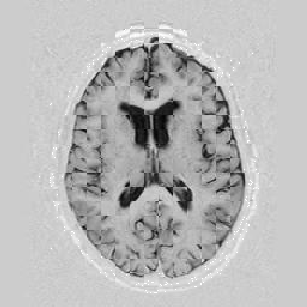

Lastly, Figure [*] shows 10 iterations at level 2, 6 iterations at level 1, and 6 at level 0.

Figure: Multi-scale NRR. From left to right, top then bottom: before NRR; after 10 iterations of NRR at level 2; after another 6 iterations of NRR at level 1; after 6 more iterations at level 0.